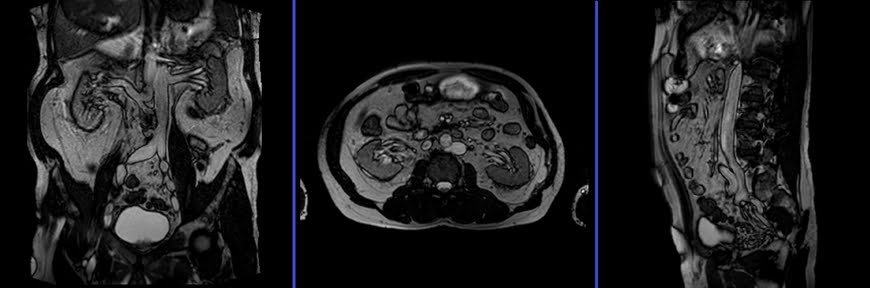

MRI Urography localizer

A three-plane T2 TRIFISP\HASTE localizer must be taken initially to localize and plan the sequences. These are fast single-shot localizers with under 25s acquisition time, which are excellent for localizing vascular structures. Take at least 5-8 slices in all planes to get the best results.